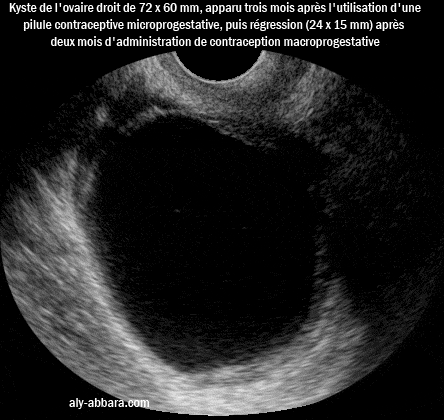

• Il s'agit d'un kyste ovarien droit, uniloculaire, à paroi fine, sans végétations endophytiques ni exophytiques ; il mesure 72 x 60 mm de diamètre, il est apparu rapidement après trois mois d'utilisation de contraception microprogestative par voie orale, à action périphérique sans blocage de l'ovulation.

• La deuxième image montre le même kyste après deux mois d'administration de pilule macroprogestative inhibiteur de l'ovulation ; on peut observer la nette régression de la taille du kyste (24 x 16 mm de diamètre).

• Donc il s'agit d'un kyste fonctionnel de l'ovaire droit.